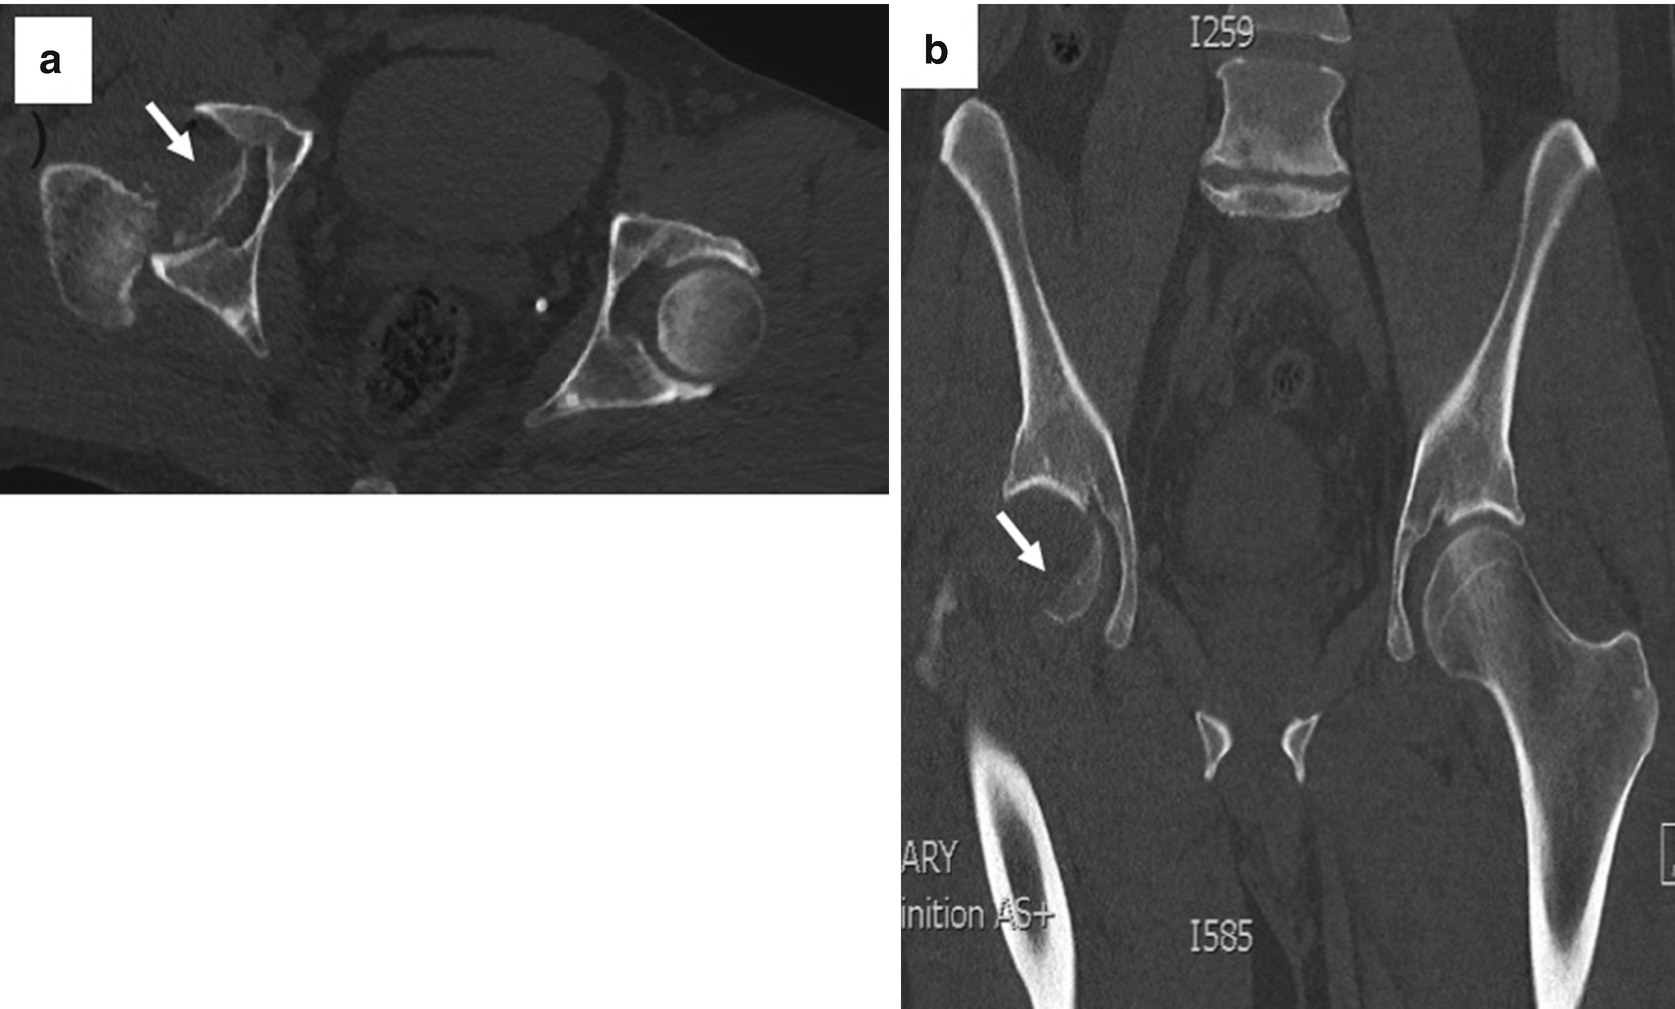

1 25 Mm Thick Ct Image Of Corona Mortis Download Scientific Diagram

Prospective Diagnosis Of Corona Mortis Hemorrhage In Pelvic Trauma Sg Trauma